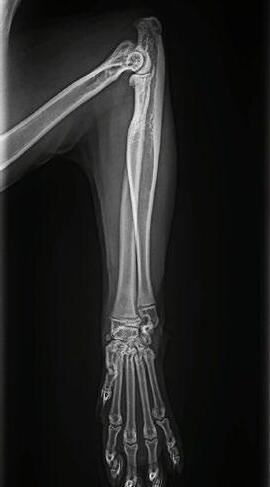

These radiographs are from a 9-month-old cat found by the side of the road ( Figure 1 A&B).

Figure 1. Lateral (A) and DV (B) radiographs from a 9-month-old kitten suspected of having focal osteomyelitis

A. The cat had focal mid diaphyseal osteomyelitis, presumably after penetrating injury, possible after a cat bite wound

B. The cat was started on Amoxyclav (20-25 mg/kg BID), repeat radiographs were planned to monitor the cat’s progress

2A 1B 2B

and lateral (B&C) radiographs from a 9-month-old kitten suspected of having focal osteomyelitis 4 weeks after starting amoxicillin clavulanate

After 4 weeks of Amoxyclav 20-25mg/kg bid (Figure 2 A,B&C) the kitten was clinically normal and non-painful to palpate over the affected area. He was continued on a further 4 weeks of Amoxyclav.

On final recheck and radiograph he was clinically normal and antibiotics were discontinued.